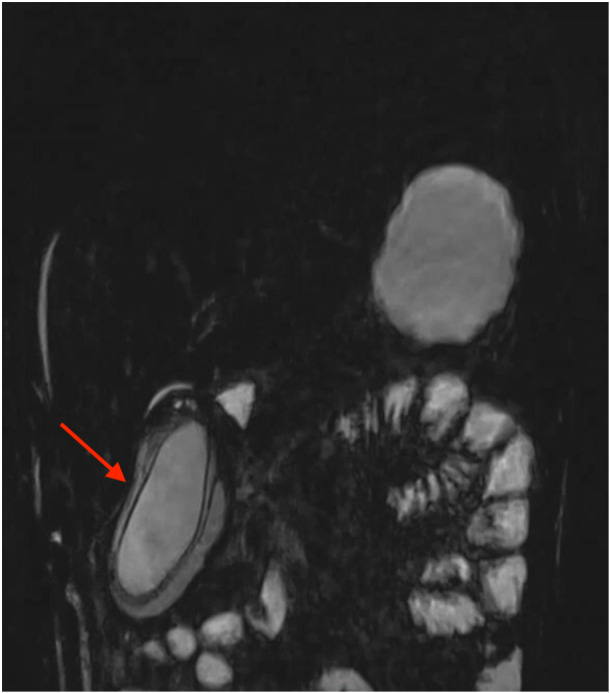

Gallbladder volvulus (GV) involves the rotation of the gallbladder along its axis, resulting in torsion. This pathology is rare, more commonly found in elderly females, but can occasionally occur in pediatric patients. Diagnosis is challenging due to often atypical symptoms, with imaging and laboratory findings typically nonspecific. Prompt surgical intervention is necessary when GV is suspected to prevent significant systemic illness. Laparoscopic cholecystectomy has proven to be safe and effective in pediatric cases. In this report, we present a pediatric case of GV, initially misdiagnosed as viral-induced acalculous cholecystitis, which was effectively managed using laparoscopic cholecystectomy.